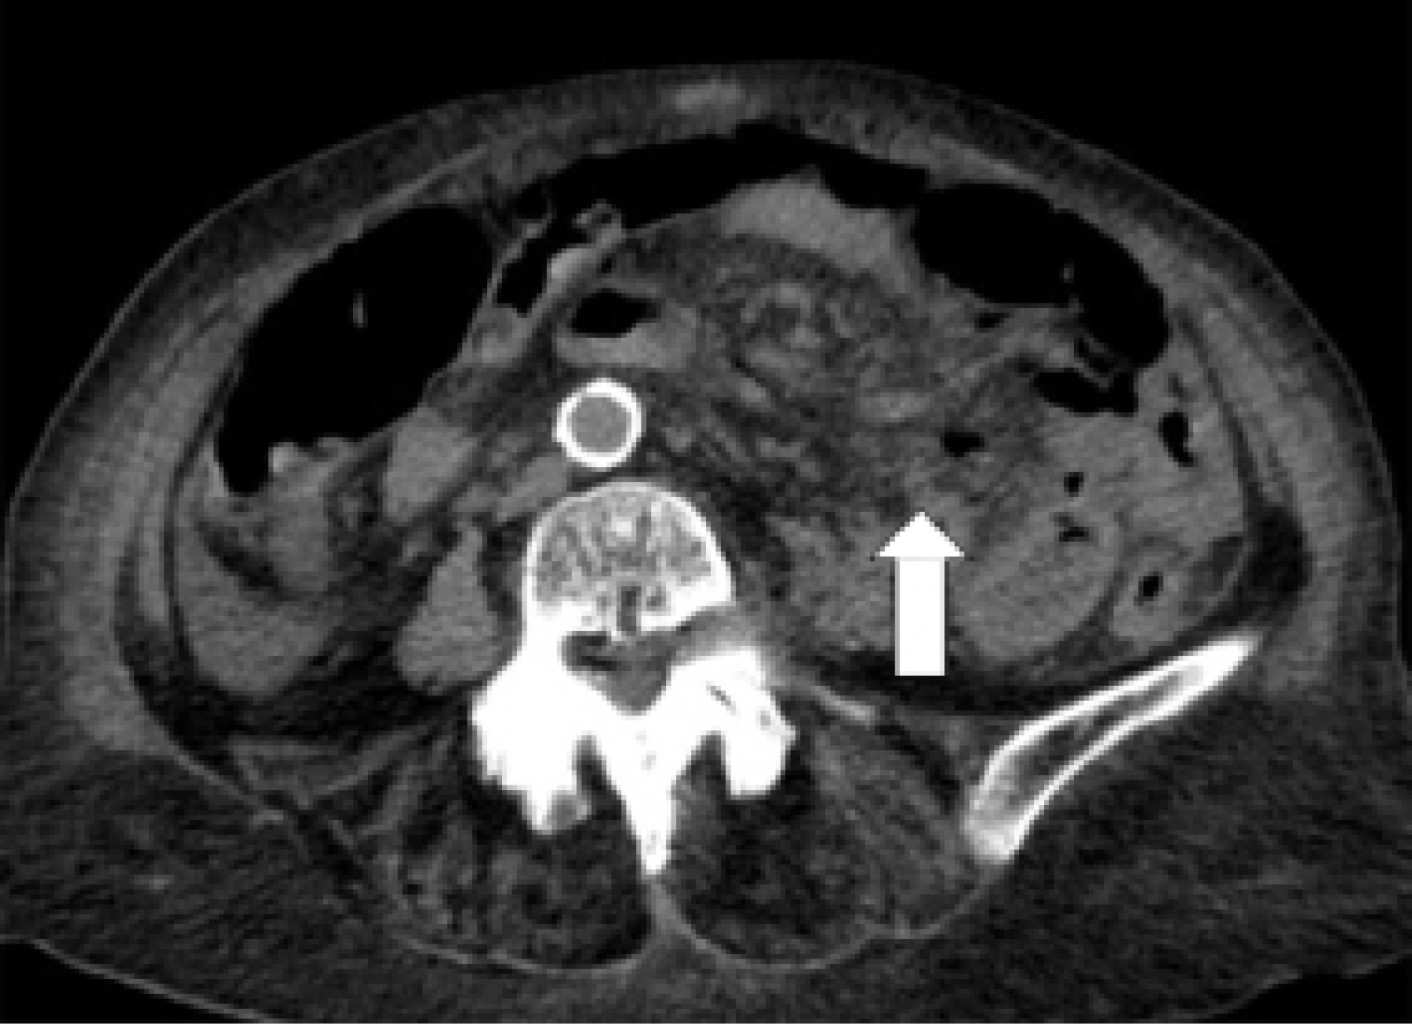

Laboratory studies reported leukopenia (3.07 × 109 l), neutrophilia (84%), hyperprocalcitoninemia (2.29 ng/ml), metabolic acidosis (pH 7.31, pCO2 27.9 mmHg, HCO3 15.8 mmHg) and hyperlactatemia (5.90 mmol/l). The rest of the laboratory tests were within normal ranges. A simple tomography of the abdomen showed pneumobilia, pneumoperitoneum, and a transition zone associated with the "whirlpool sign" in jejunum topography in a closed loop (Figure 1); and free fluid in the right parietocolic gutter (Figure 2).

Figure 2